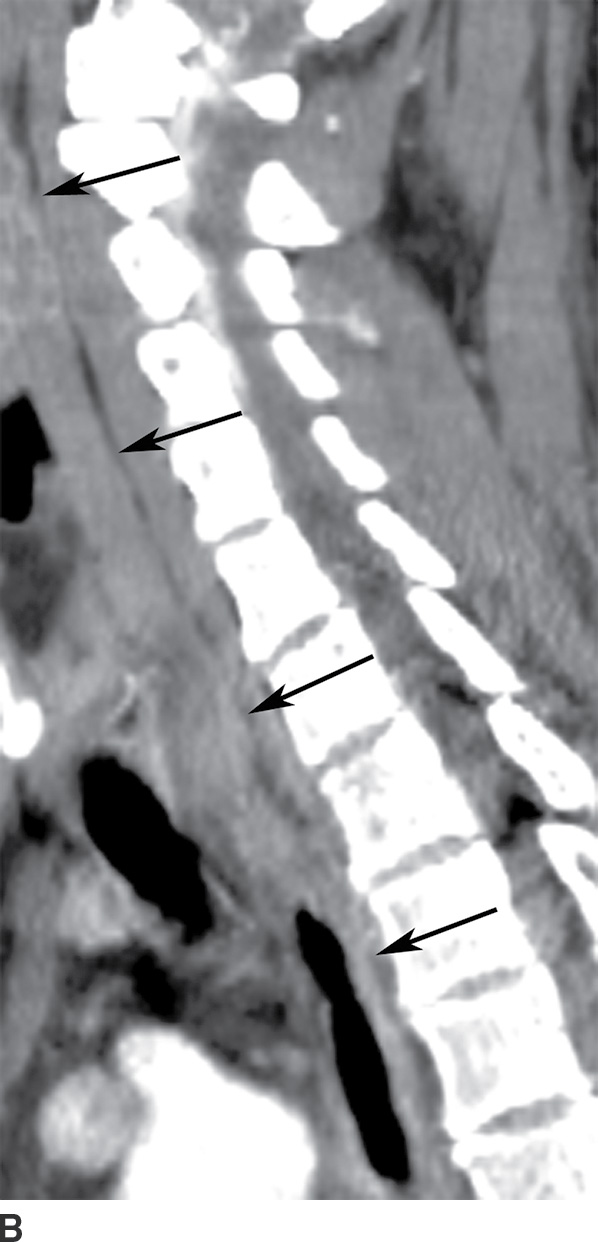

Figure 5 from Computed tomography imaging of deep neck space infections Danger Space Radiology Learn about the anatomy and pathology of the deep spaces of the head and neck, which are compartments delimited by the. Learn about the danger space, a deep compartment of the head and neck that can be infected and spread to the thorax. Because the alar fascia is very thin, the danger space and true retropharyngeal space cannot be distin. Danger Space Radiology.